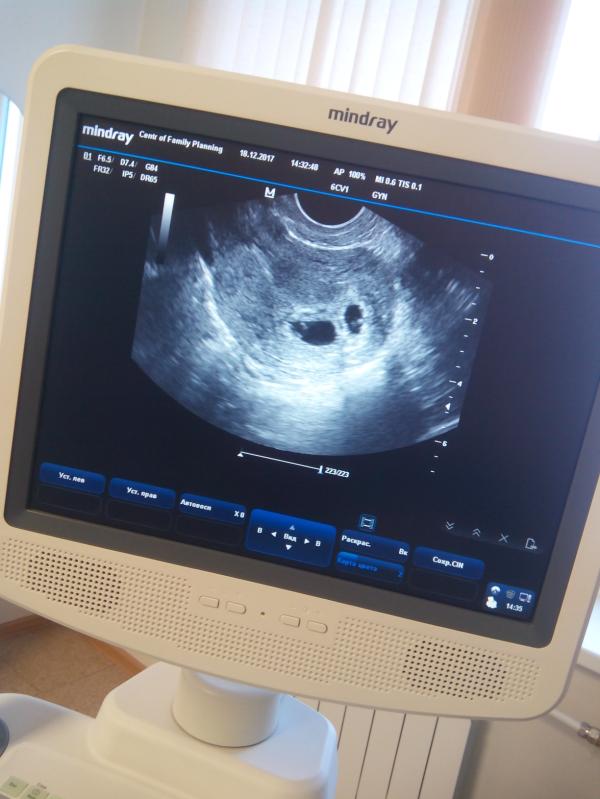

Ура наше первое УЗИ 😍 знакомство с нашими малышами)) все у нас хорошо) все соответствует сроку) двойня как и предполагал врач) Дай бог чтоб беременность была легкой 🙌😍